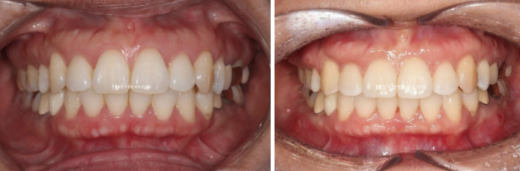

After 1 year and 7 months of treatment, here are the before-and-after comparison photos.

Since the original alignment and bite were good, there is not much difference in the intraoral photos other than improvement in the angle of the protruded front teeth.

22.09~24.04

A fairly significant amount of self-rotation of the mandible occurred due to the intrusion and posterior movement of the entire dentition. Although treatment generally aims for about 2 mm, around 3 mm occurred.

The area that appeared to be chin retrusion improved, and the orange-peel chin relaxed, making the line from the lower lip to the chin look more natural.

When self-rotation occurs, the chin tip moves upward, and the vertical length of the lower face looks shorter from the front, making it appear smaller.

Also, due to self-rotation, the chin tip moves forward slightly.

The most noticeable effect is that protrusion has been corrected, allowing the lips to close comfortably.

The nasolabial folds, which many patients worry about, did not become deeper than they were at the beginning.